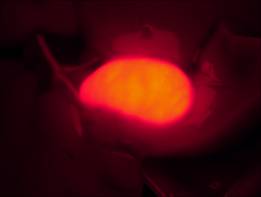

明美體視熒光顯微鏡應(yīng)用于藥物檢測實驗

[客戶實驗方法] 以小白鼠作為實驗動物模型,通過體視熒光顯微鏡觀察實驗組和對照組,在同一參數(shù)設(shè)置下,用明美成像系統(tǒng)分析軟件將明場、熒光分別拍攝的效果圖合成,檢測藥物作用部位。

藥物膽熒光